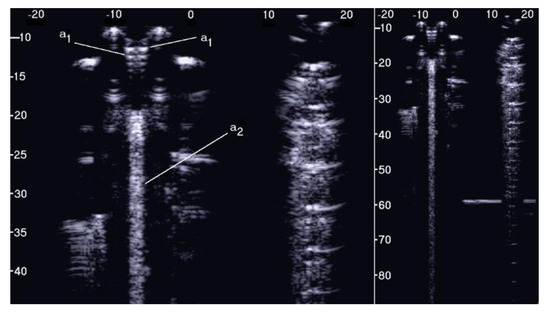

The PVC box, which is shown in the right image of Figure 1, was designed to test the ultrasound response to different distributions of air cylinders. The first test shows what happens when a single row of air cylinders is introduced in the agar gel. The image on the left of Figure 6 shows that in this case, there are no artifacts except the short ones which are generated by multiple reflections between two contiguous air cylinders. In fact, a distance of about 0.5 mm between two replicas of the repetitive pattern can be derived from Figure 6 according to the assumed propagation speed of 1500 m/s. In particular, no artifact is generated by a single air cylinder. The situation changes, however, as a row of air cylinders is added, and increasingly longer artifacts are observed as the number of rows of cylinders increases. The two images in the centre and on the right of Figure 6 show the artifacts which were obtained with two and with four rows of air cylinders, respectively. A repetitive pattern is still perceivable, but it is not clearly quantifiable. The thick white lines at the bottom of the three images are given by the reverberations within the bottom wall of the box.

Figure 6. The image on the left shows how a single row of air cylinders does not generate vertical artifacts. The two images in the centre and on the right show the artifacts obtained with two and with four rows of air cylinders. A different zoom degree has been used for the image on the right.